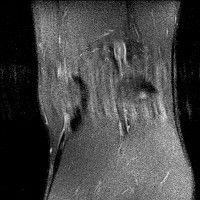

무릎 mri 간단히 봐주실 수 있으시나요 ㅠㅠ

안녕하세요 8년전 십자인대 수술하고 최근 무리한 운동에 무릎 불편감이 생겨서

mri 찍었습니다.

진단결과는 첫 찍은 병원에서 활액막염 이라는 진단을 받았습니다. 혹시 봐주실 수 있으실까요?

올라온 MRI가 단편적이라서 정확한 진단에 어려움이 있지만 십자인대에는 큰 이상이 있지는 않은것 같으며, 무릎관절내 물이 있는 것으로 보아 활액막염의 진단이 맞을 것 같습니다.

하지만 단편적인 영상이기 때문에 촬영병원에서 정확한 판독지 등을 받으시는 것이 좋겠습니다.